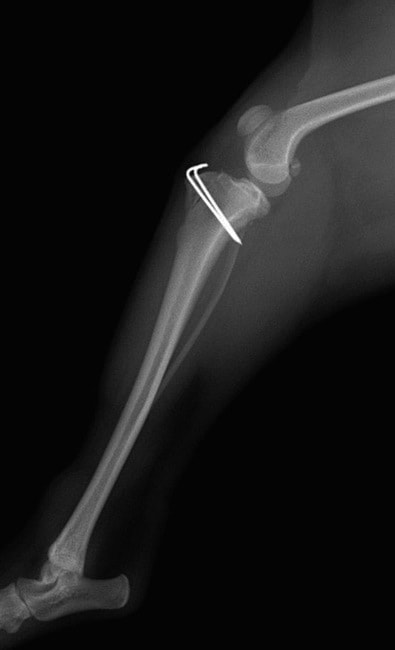

■ 症例24 キャバリア 7か月

左右膝蓋骨内方脱臼(左:グレードⅣ 右:グレードⅢ)

以前から左右後肢の跛行が認められ、整形外科学的検査・レントゲン検査により左右の膝蓋骨脱臼が認められた。症状が重度である左膝の膝蓋骨脱臼整復術を行った。外科手技は縫工筋及び内側広筋の解放、脛骨粗面の外側転位、滑車ブロック形造溝術、内外側関節方の縫縮を実施した。術後一か月時点で、左の膝蓋骨は安定しており経過は良好である。

本症例は成長期における重度の膝蓋骨脱臼であり、術後の再発の可能性もあるため、経過をしっかりと観察していく必要がある。また、今回手術を実施していない右膝に関しても経過を観察し、手術を検討していくこととする。